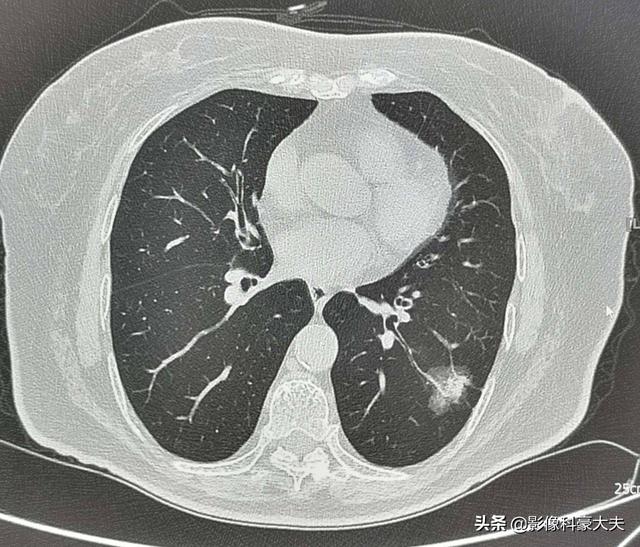

例えば、左下肺に2.2cmの混合膜ガラス結節があるこの中年女性は、リスクの高い結節であり、実際、肺腺癌の典型的な徴候を有している。血管の進入と肥厚を伴う明瞭な地硝子影、気管支気腹徴候、遠位胸膜浸潤、浸潤性肺腺癌の外科的病理所見このような病変は経過観察には勧められないので、転移や治療の遅れを避けるために、さらに詳しく調べてはっきりさせる必要がある。

しかし、すべての高リスク結節が肺癌であるわけではなく、上記の高リスク基準より小さい結節も肺癌である可能性があることも認識する必要がある!ガイドラインは、私たちのために輪になっているだけです。